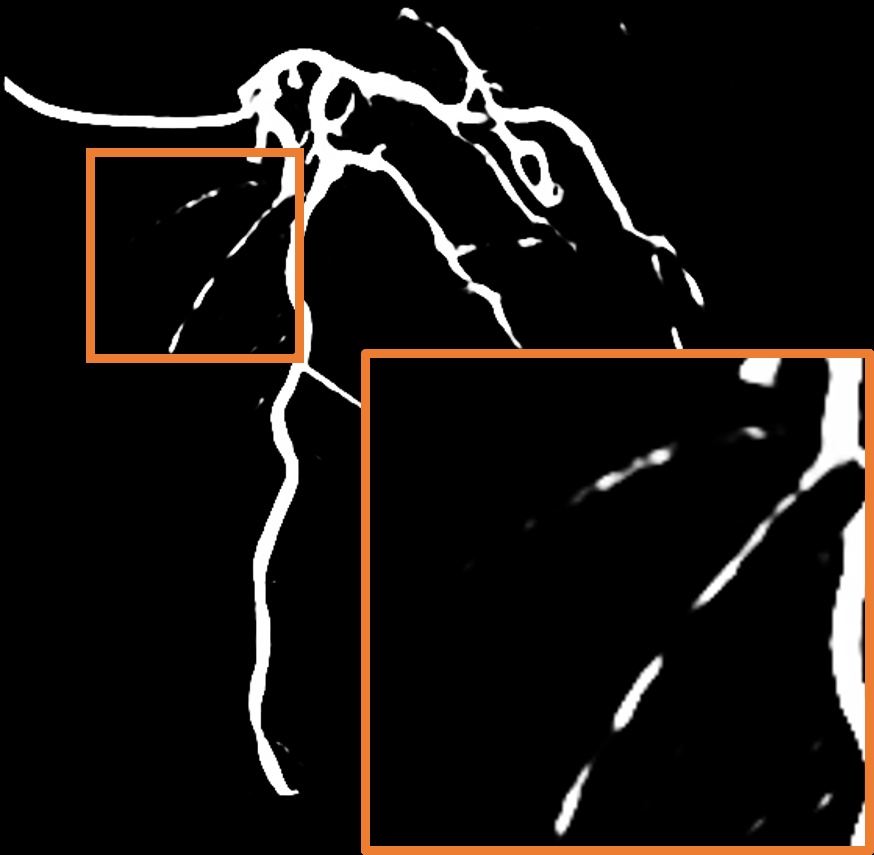

Parallel vessel motion loss .

We conduct an experiment to assess the effect of the parallel vessel motion loss by removing it from the training pipeline. As shown in Table 2, the segmentation performance decreases the Dice score by 0.0047. Without this loss to enforce parallelism between blood and vessels, the segmentation results are negatively affected. In addition, the comparison between without and with is shown in Figure 8 (c). The zoom-in patch shows that the image with has clearer segmented vascular regions.